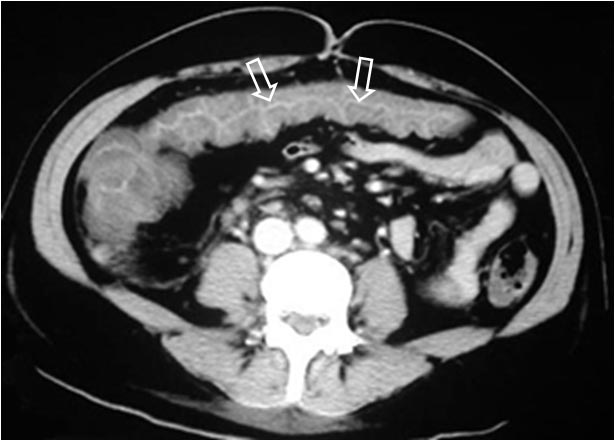

Signo de edema o inflamación severa del colon, de cualquier etiología, visto en TC. Corresponde al engrosamiento de la pared del colon con retención del contraste oral entre las haustras engrosadas (flevchas), aunque el signo también puede estar presente en TC sin contraste. Fue descrito inicialmente en la colitis por Clostridium difficile (colitis pseudomembranosa), pero después se ha demostrado que no es específico, pudiendo estar presente en otras colitis infecciosas por otros gérmenes (Salmonella, citomegalovirus,…) en colitis isquémica, en vasculitis (lupus) e incluso en el edema relacionado con cirrosis.

Otras imágenes del signo en otro paciente. Cortes axial (derecha) y sagital (izquierda), donde se observa la afectación del ángulo hepático del colon.